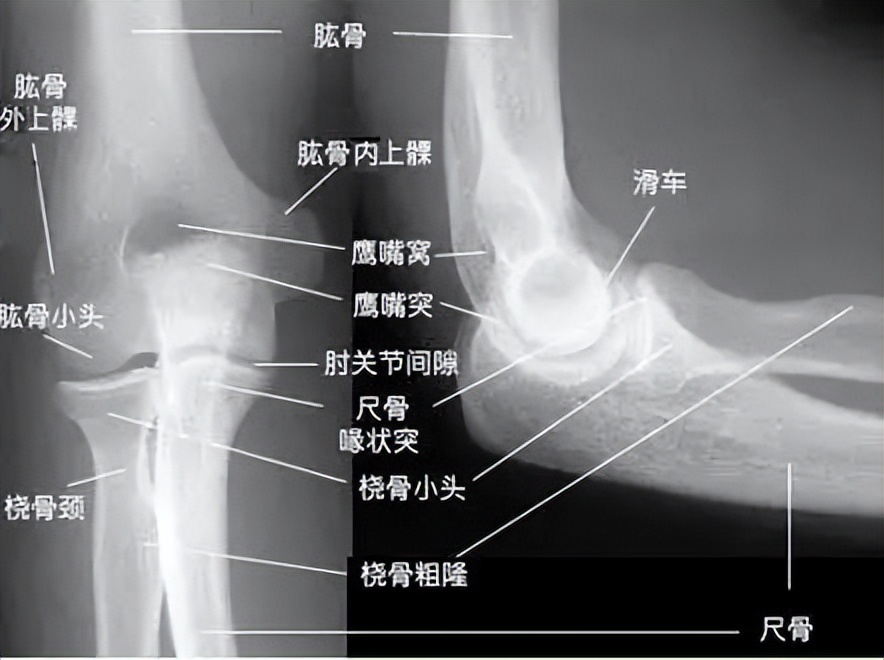

肱骨外上髁炎又称“网球肘”,主要是伸肌总腱起始部(即是肱骨外上髁部)的损伤和撕裂所产生的慢性无菌性炎症,临床上以肘部外侧部(如下图)疼痛为主。

5.X线检查阳性